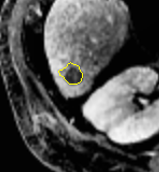

We first introduce a method for connecting the output of a CNN to an ACM, yielding a model for the precise delineation of lesions, to which we refer as Deep Active Lesion Segmentation (DALS) (Figure 4). We then go further to introduce a truly unified framework (Figure 5) that bridges the gap between ACMs and CNNs by leveraging a novel, automatically differentiable level-set ACM with trainable parameters that allows for back-propagation of gradients and can be end-to-end trained along with a backbone CNN from scratch, without any CNN pre-training. The ACM is initialized directly by the CNN and utilizes an energy functional that is locally-tunable by the backbone CNN, through 2D feature maps. Thus, our work overcomes the big hurdle of fully automating the powerful ACM approach to image segmentation. We have applied our proposed framework to the task of building segmentation in aerial images (Figure 6).

Deep Active Lesion Segmentation

[45]: Lesion segmentation is an important problem in computer-assisted diagnosis that remains challenging due to the prevalence of low contrast, irregular boundaries that are unamenable to shape priors. We introduce Deep Active Lesion Segmentation (DALS), a fully automated segmentation framework that leverages the powerful nonlinear feature extraction abilities of FCNs and the precise boundary delineation abilities of ACMs. Our DALS framework benefits from an improved level-set ACM formulation with a per-pixel-parameterized energy functional and a novel multiscale encoder-decoder CNN that learns an initialization probability map along with parameter maps for the ACM. We evaluate our lesion segmentation model on a new Multiorgan Lesion Segmentation (MLS) dataset that contains images of various organs, including brain, liver, and lung, across different imaging modalities—MR and CT. Our results demonstrate favorable performance compared to competing methods, especially for small training datasets. -

First, we introduce a fully automatic framework for medical image segmentation that combines the strengths of CNNs and level-set ACMs to overcome their respective weaknesses. We apply our proposed Deep Active Lesion Segmentation (DALS) framework to the challenging problem of segmenting lesions in MR and CT medical images, dealing with lesions of substantially different sizes within a single framework. In particular, our proposed encoder-decoder architecture learns to localize the lesion and generates an initial attention map along with associated parameter maps, thus instantiating a level-set ACM in which every location on the contour has local parameter values.

By automatically initializing and tuning the segmentation process of the level-set ACM, our DALS yields significantly more accurate boundaries in comparison to conventional CNNs and can reliably segment lesions of various sizes.

Our DALS framework is illustrated in Figure 3. The boundaries of the segmentation map generated by the encoder-decoder are fine-tuned by the level-set ACM that takes advantage of information in the CNN maps to set the per-pixel parameters and initialize the contour. The input image is fed into the encoder-decoder, which localizes the lesion and, after convolutional and sigmoid layers, produces the initial segmentation probability map , which specifies the probability that any point lies in the interior of the lesion. The Transformer converts to a Signed Distance Map (SDM) that initializes the level-set ACM. Map is also utilized to estimate the parameter functions and in the energy functional (7). Extending the approach of Hoogi et al. [54], the functions in Figure 3 are chosen as follows: